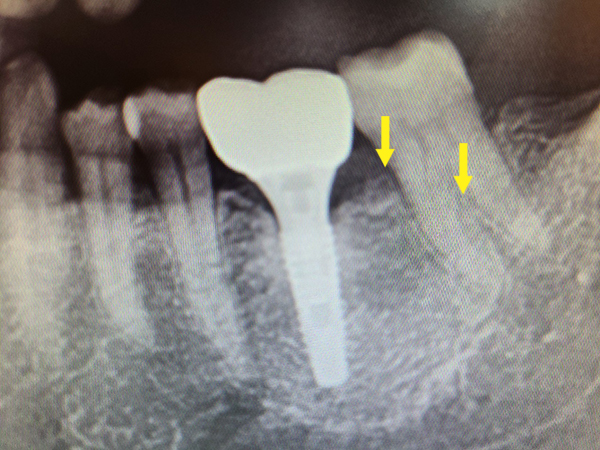

牙根分岔區及前方牙根可見黑色骨流失(紅色箭頭處),經牙周再生手術後,使用人工骨粉及生長因子重建失去之齒槽骨,三年後可見X光片上更緻密之白色影像(黃色箭頭處)。

術前:![]() |

術後:![]() |